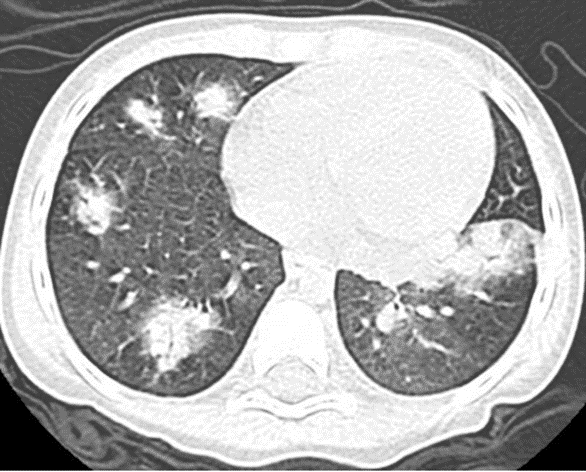

(7)免疫抑制患者的经验性抗水痘-带状疱疹病毒指征,①临床特征:双肺多发结节浸润伴水疱性皮疹。②治疗推荐:阿昔洛韦10~15 mg/kg q8h。